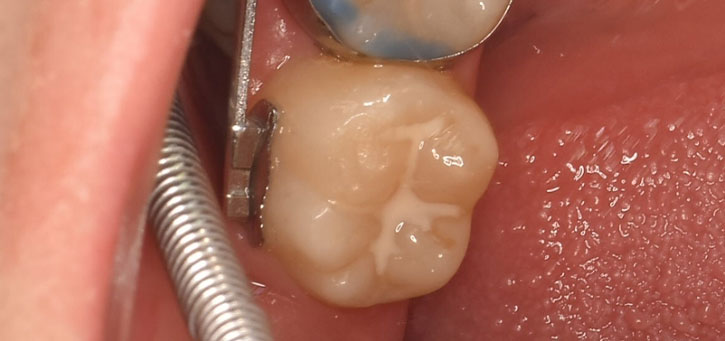

シーラント(保険適用)

奥歯の溝を薄いフッ素含有の樹脂で塞ぐ虫歯予防法です。奥歯の溝は複雑な形をしているので虫歯になってしまうことがありますが、シーラントで奥歯の溝を塞ぐことにより虫歯を防ぐことが可能です。